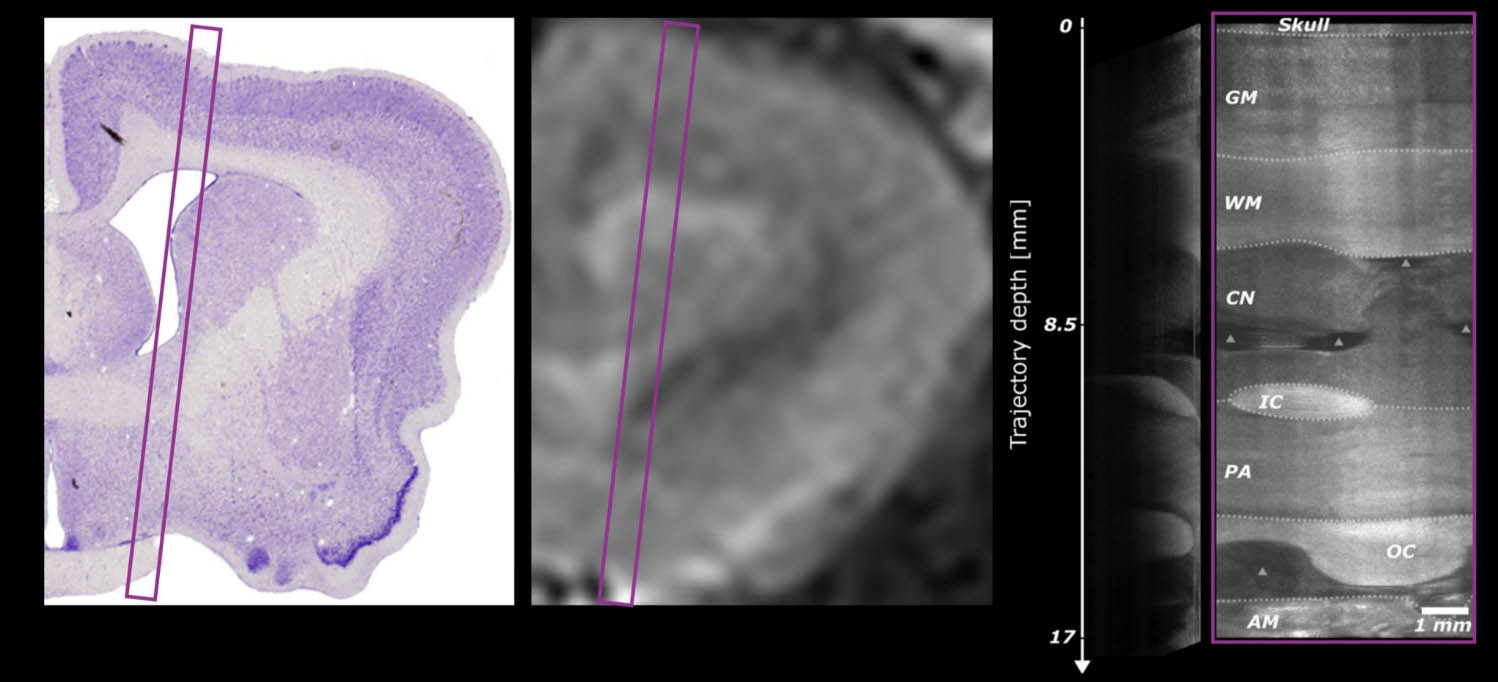

The core imaging modality behind Neuro Access is optical coherence tomography (OCT), a minimally invasive technique that can help neurosurgeons visualise brain anatomy and critical structures in real time during stereotactic procedures. While OCT provides rich structural information, interpreting the signal in real time during surgery is inherently challenging. This is where machine learning becomes central. Clee Medical is developing algorithms that automatically segment tissue structures within the signal to highlight anatomical boundaries, vasculature, and tissue transitions in real time.

In a DBS procedure targeting the subthalamic nucleus, for instance, the system can recognise characteristic tissue signatures along the trajectory and provide visual feedback to confirm the surgeon is approaching the intended structure. In oncology applications, similar models could flag transitions between healthy and pathological tissue. “The goal is to provide real-time intelligence that helps surgeons navigate with greater confidence,” Lapinski says, “leading to faster surgeries, increased capacity, and more consistent outcomes for patients.”